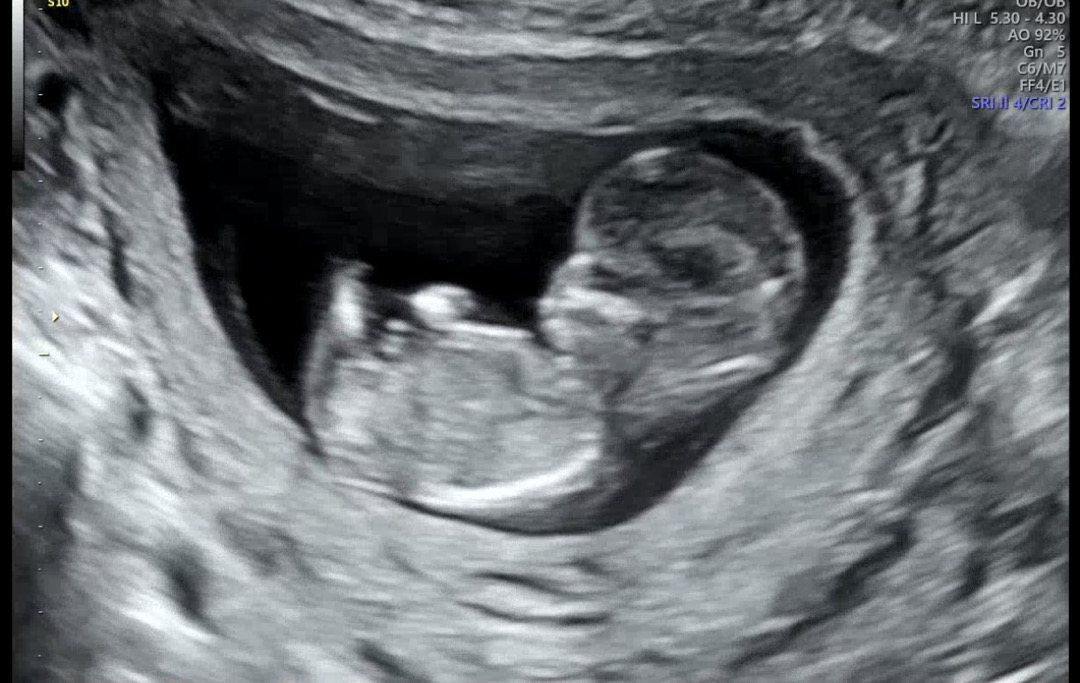

12주차 성별 초음파 봐주세요오🥹💗

병원에선 원장님이 허벅지랑 다 보더니 확실하진않지만 아직까진 뭐가 안보여서 딸같다는데..투표 ㅂ부탁드려요!